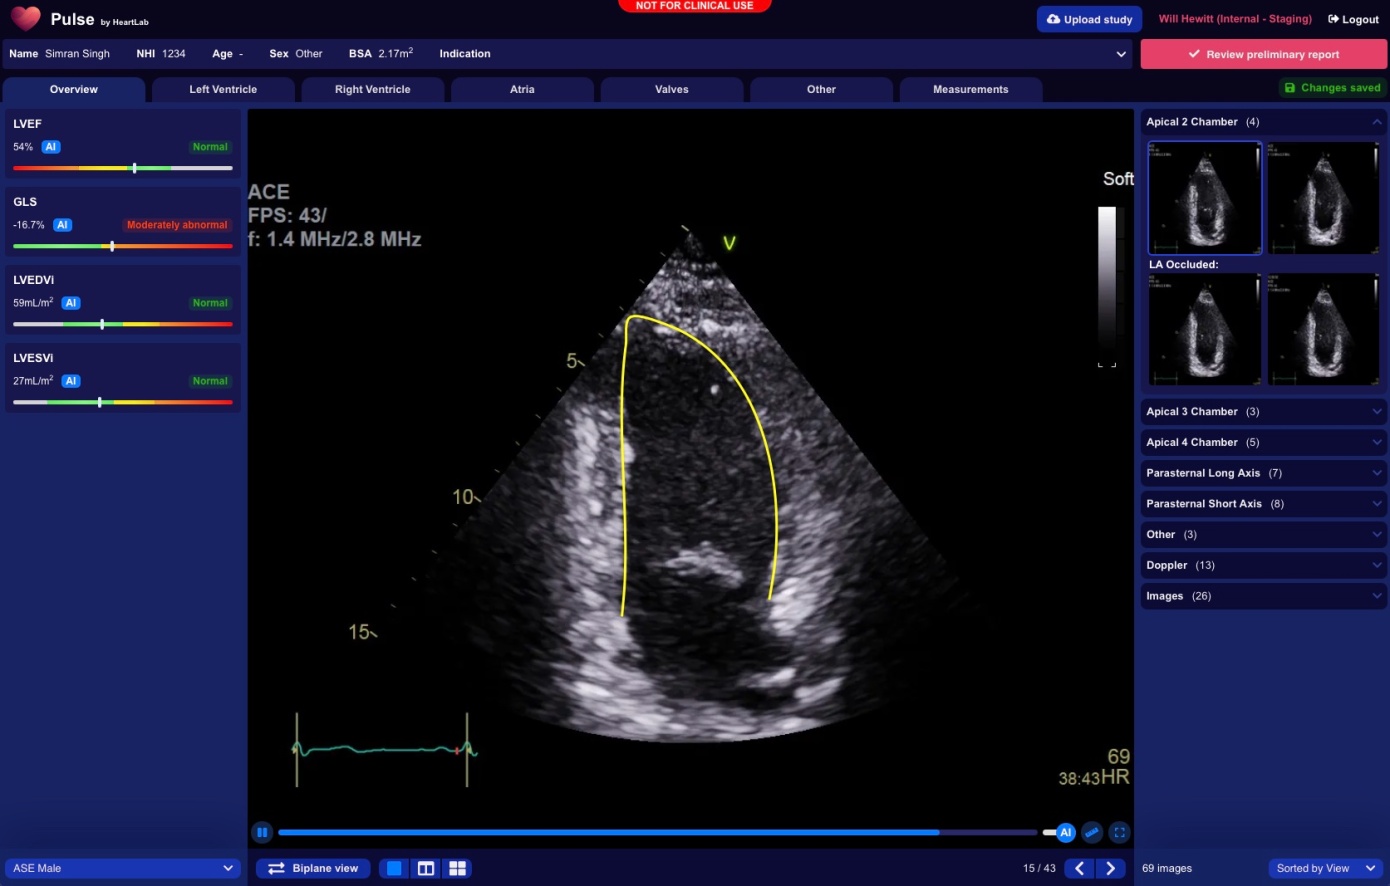

HeartLab занимается разработкой инновационного ПО на основе искусственного интеллекта, направленного на работу с эхокардиографией — видом УЗИ, которое позволяет исследовать работу сердца и его клапанов, а также сосудистой системы. ИИ-инструмент от стартапа умеет расшифровывать и анализировать результаты УЗИ, сортировать снимки и составлять отчеты для медицинских карт. Такое решение не только помогает врачам увереннее ставить диагноз, но и оптимизирует рабочий процесс, освобождая время, которое тратится на ручное исследование снимков и составление отчетов.

На данный момент технология HeartLab проходит испытания в четырех медицинских центрах Новой Зеландии. Представители стартапа находятся в процессе ожидания одобрения своего продукта FDA (Управлением по санитарному надзору за качеством медикаментов США), после чего HeartLab планирует выйти на американский рынок и начать официальные продажи своего решения как SaaS. По словам Хьюитта, продукт нацелен в первую очередь на малые и средние клиники — поскольку во многих крупных кардиологических центрах есть свои инструменты, частично автоматизирующие рабочий процесс врачей.